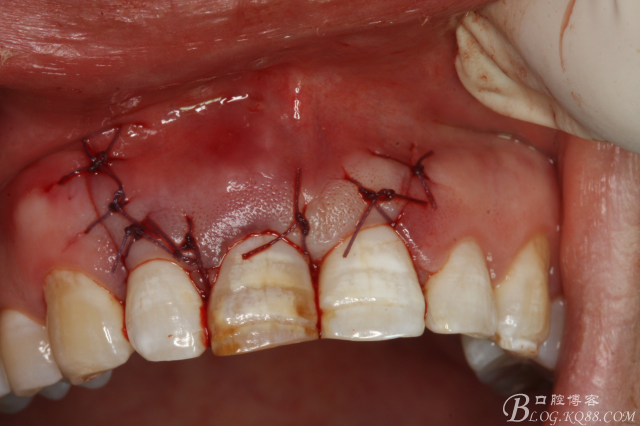

圖18.縫合